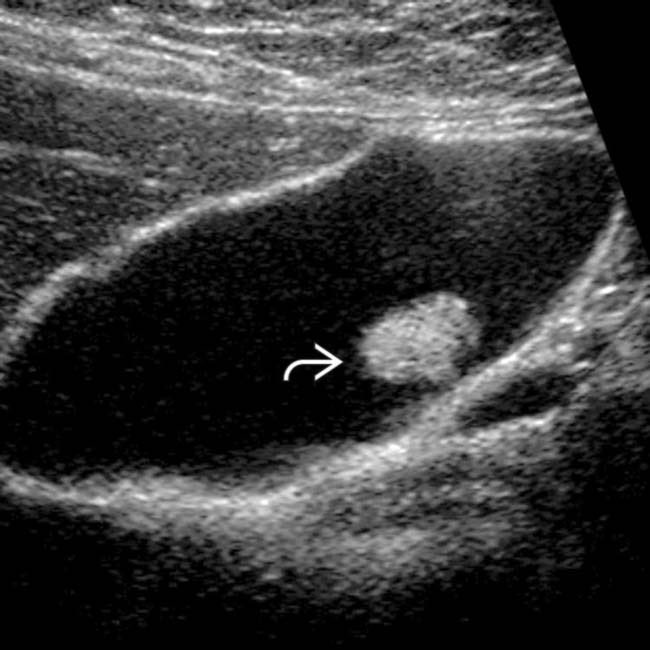

لحميات المرارة هي عبارة عن زوائد بارزة من جدار المرارة الداخلي و التي قد تنتج عن التهابات مزمنة او غيرها. تصيب فئة قليلة من المجتمع لا تتجاوز ال ٥٪ و الغالبية العظمى لا تتسبب في اي اعراض تذكر. يتم عادة اكتشافها بالصدفة لدى اجراء صونار الكبد و الكلى او المرارة.

١. حجم الزائدة اللحمية (تزال جراحيًا للتي يتجاوز حجمها ١٠ ملم)